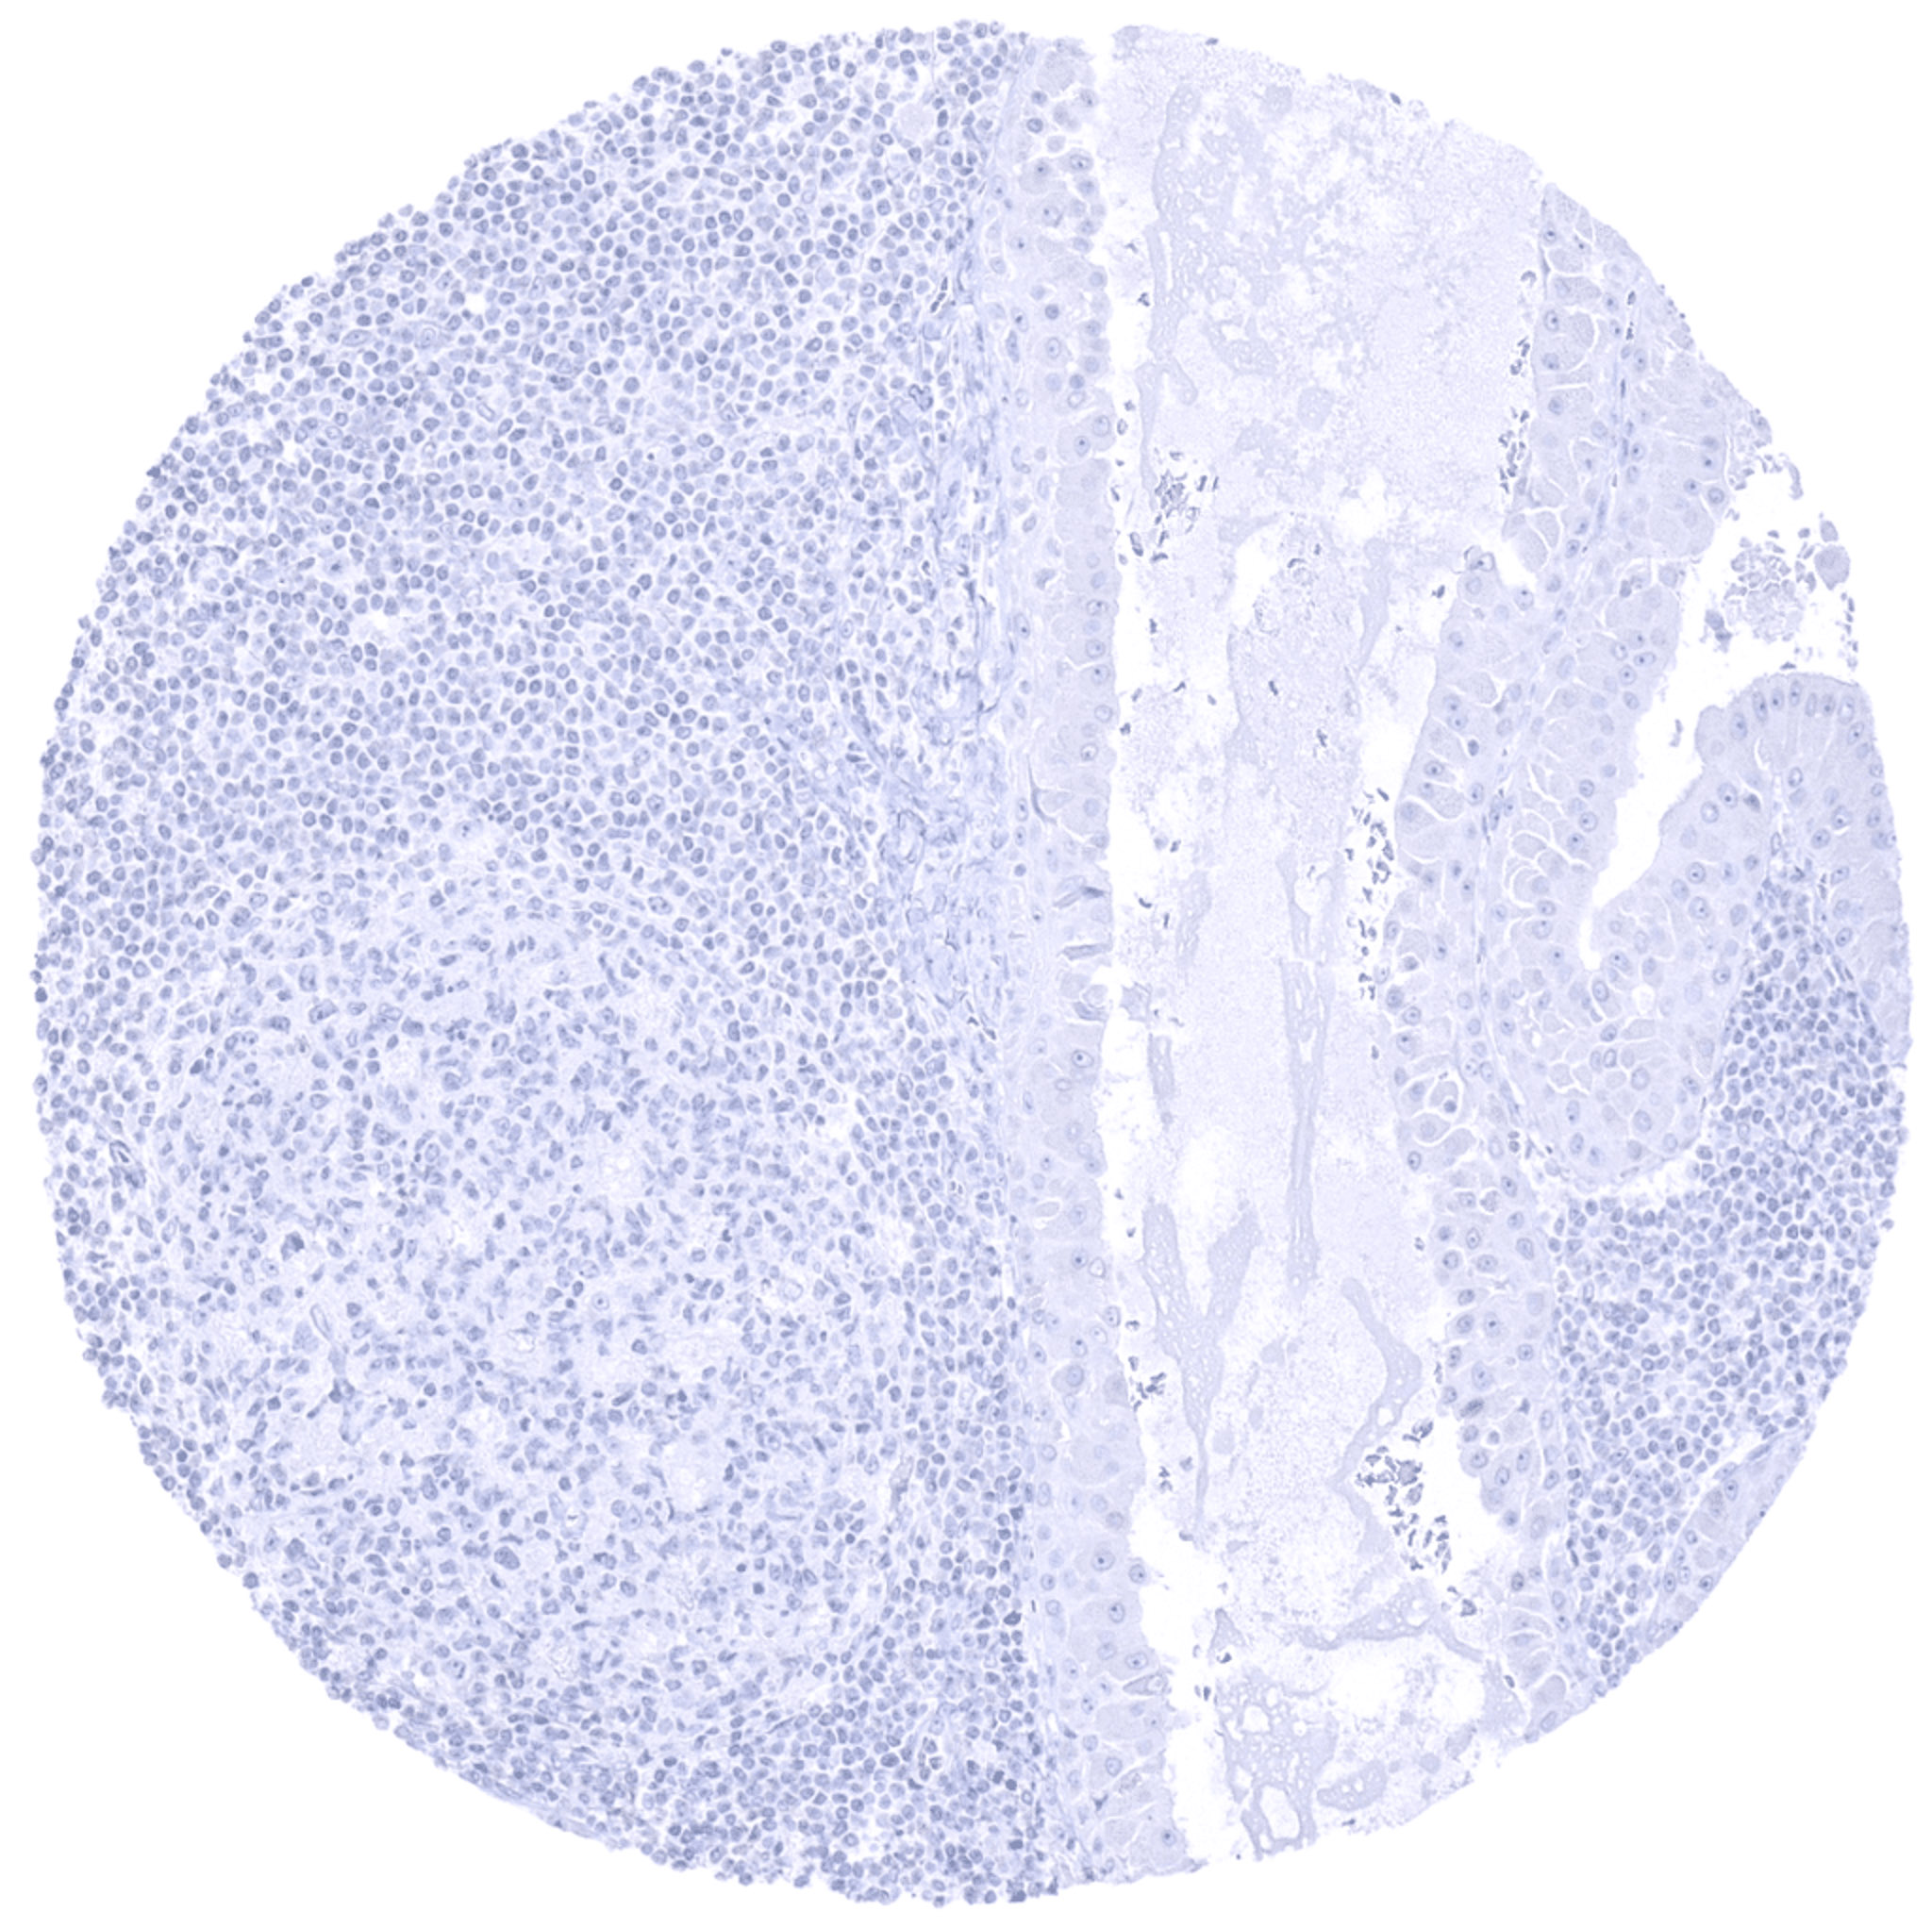

Lymph node- TdT negative diffuse large B-cell lymphoma.

Lymph node- TdT negative Hodgkin's lymphoma.